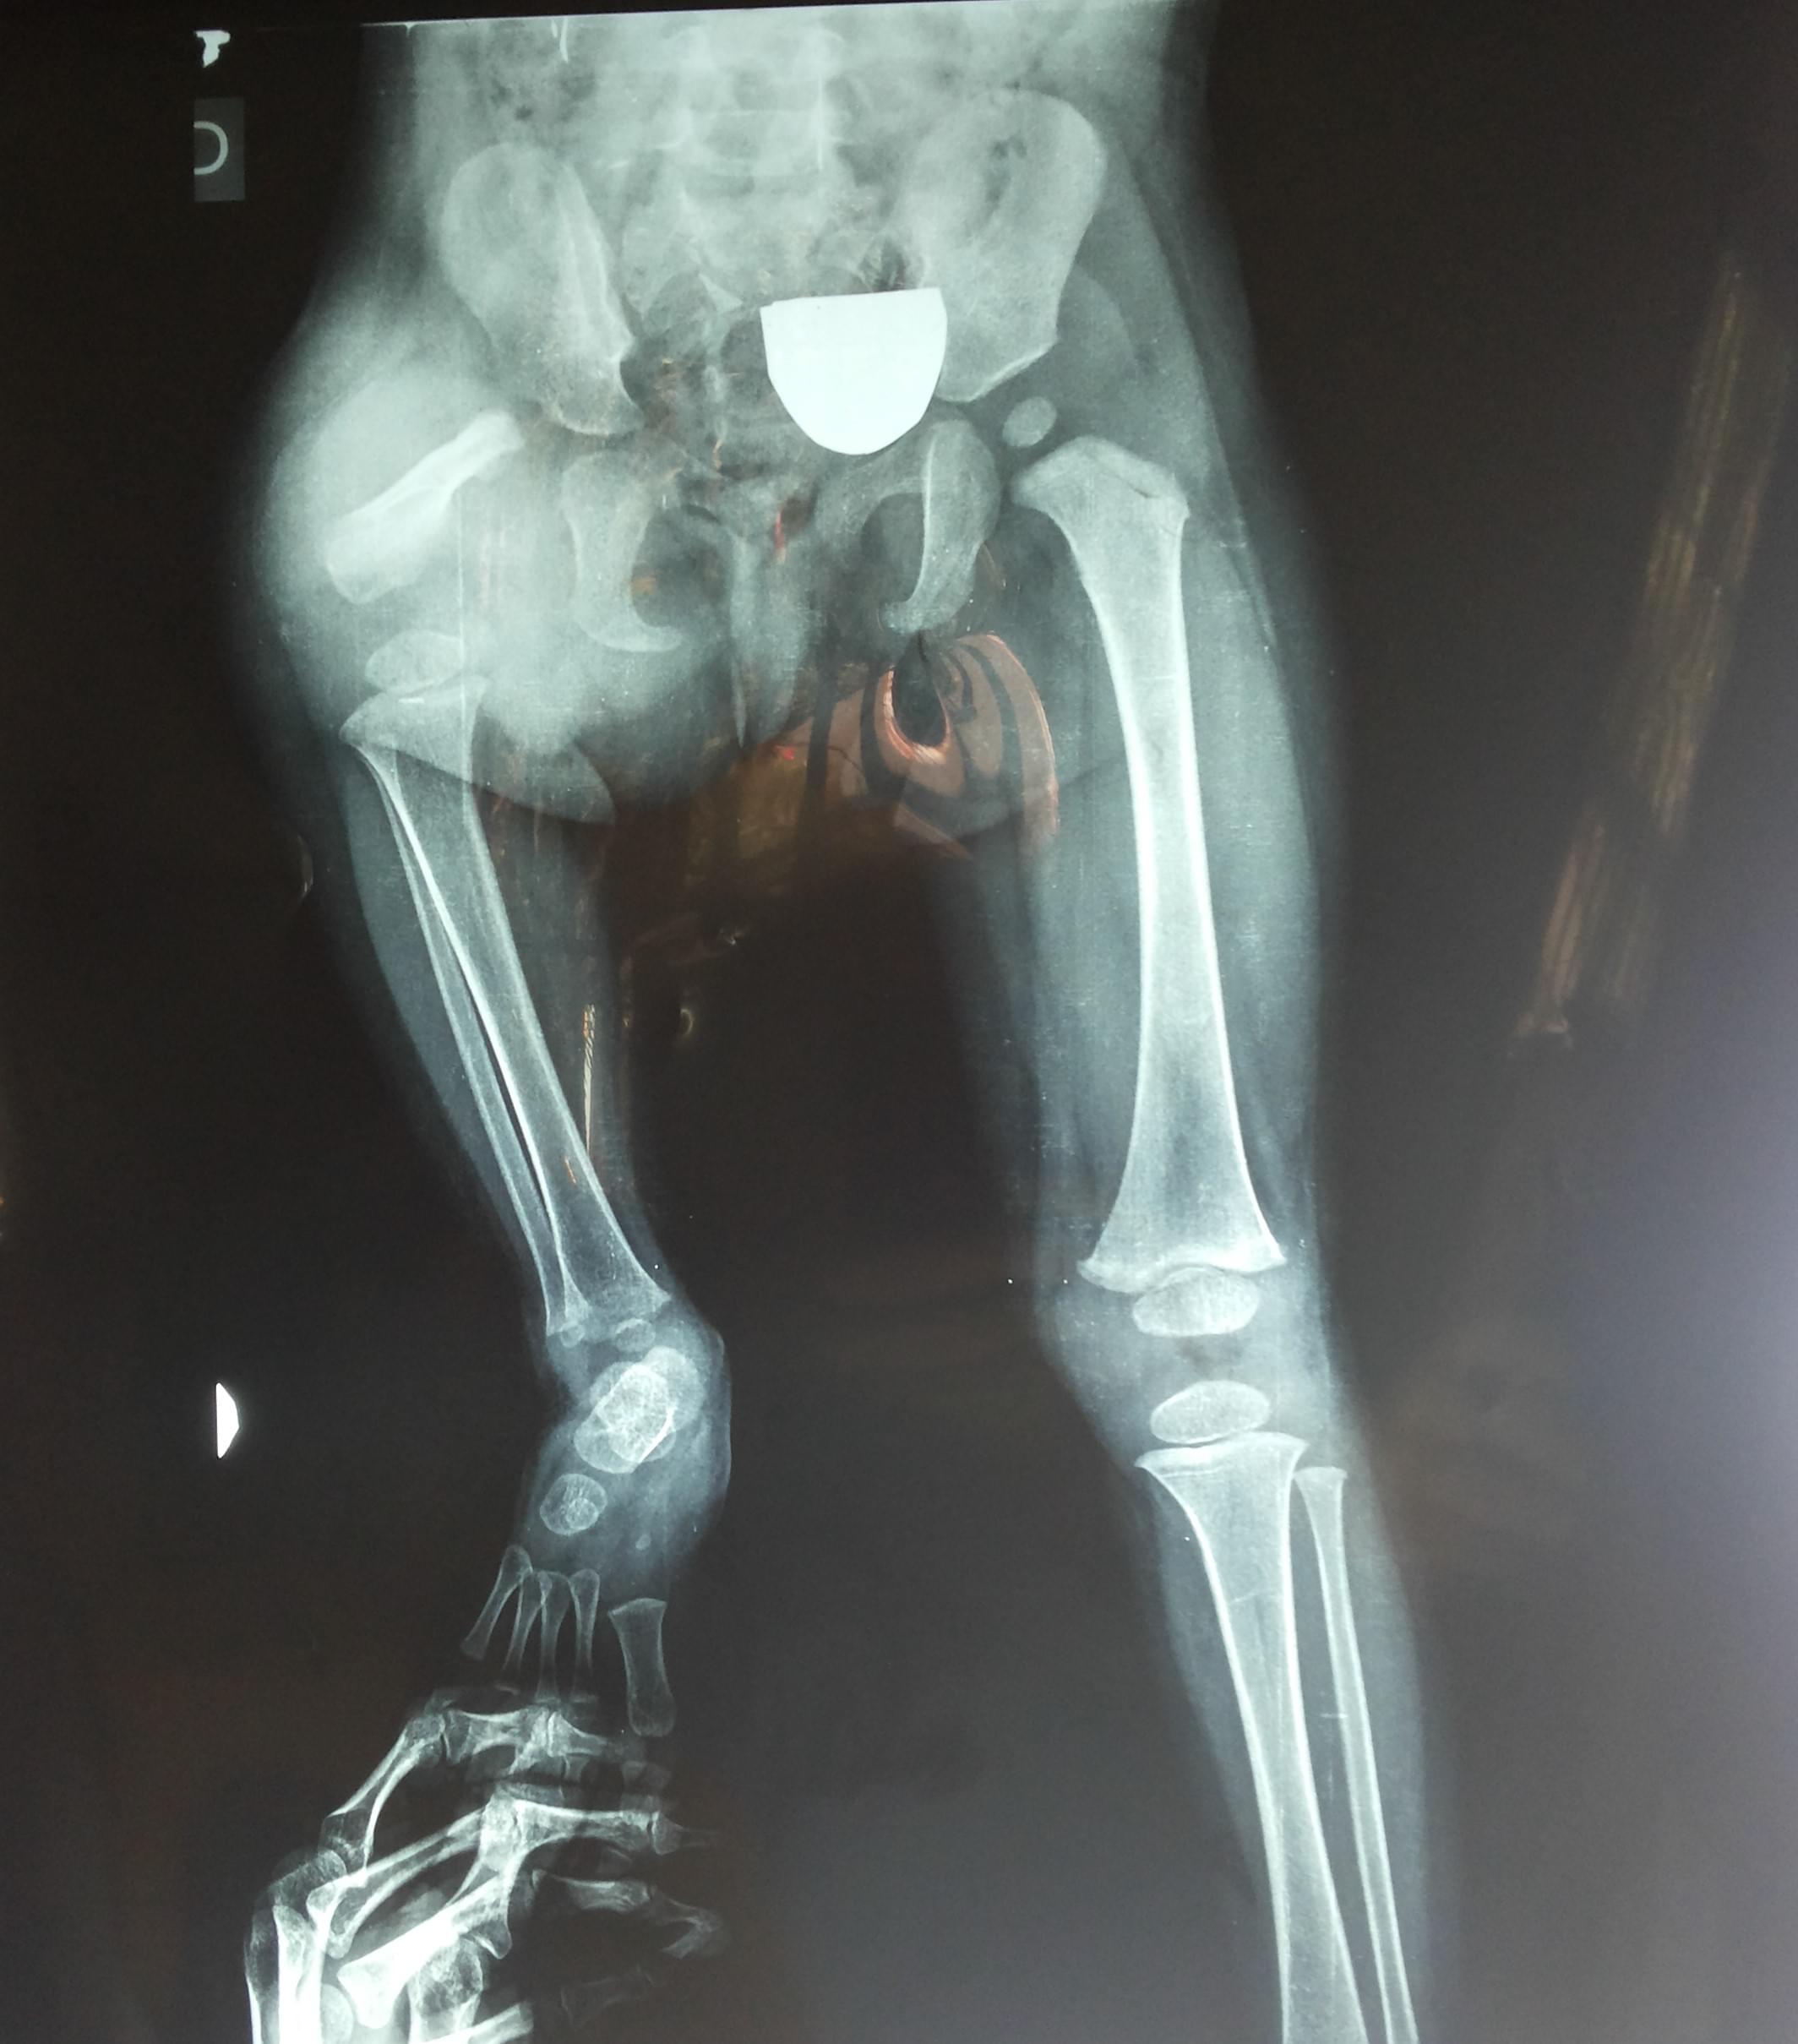

Ortopedia Infantil